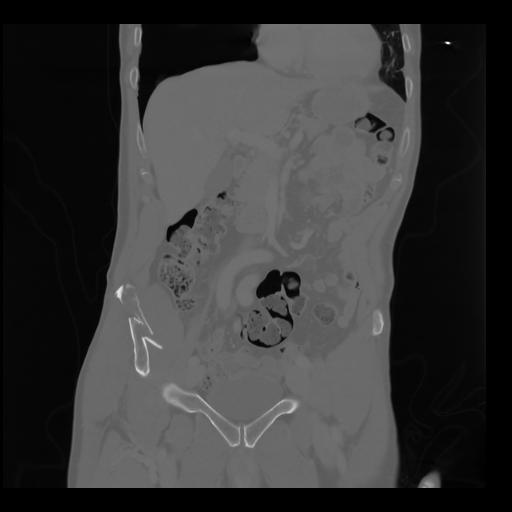

35 CUERPO,CE,Coronal,3.000,CUERPO,Coronal,